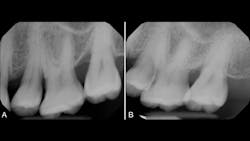

Periodontal ligament stem cells (PDLSC), located within the periodontal ligament, are of particular interest as these progenitor cells are involved in the processes of repairing alveolar bone and periodontal tissues that surround teeth. Specifically, exosomes derived from these cells (periosomes) may be the promising exosome of choice for treating gum disease. Exosomes for periodontitis (termed periosomes) have already been utilized in humans, and the results have been promising. The authors of this article have been among the first groups to investigate periosomes for bone regeneration in patients (figure 1). Periosomes exhibit essential roles in biological mechanisms, including the stimulation of cellular proliferation, angiogenesis promotion, and the enhancement of tissue repair capabilities.2

The case in Figure 1 presents a patient who was losing significant bone around a back molar. The after photo represents a new radiograph taken six months later, displaying new bone regeneration using periosomes. Stay tuned for upcoming publications from Dr. Froum and Dr. Estrin on the use of exosomes in humans.